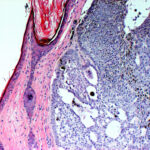

PIGMENTED BASAL CELL CARCINOMA

Pigmented BCC is a sub-type of nodular BCC that exhibits increased melanization. Pigmented BCC appears as a hyperpigmented, translucent papule, which may also be eroded (Fig. 115-3). The differential diagnosis includes nodular melanoma.

Pigmented Basal Cell Carcinoma

Pigmented BCC shows histologic features similar to those of nodular BCC but with the addition of melanin.38 Approximately 75 percent of BCCs contain melanocytes, but only 25 percent contain large amounts of melanin. The melanocytes are interspersed between tumor cells and contain numerous melanin granules in their cytoplasm and dendrites. Although the tumor cells contain little melanin, numerous melanophages populate the stroma surrounding the tumor.